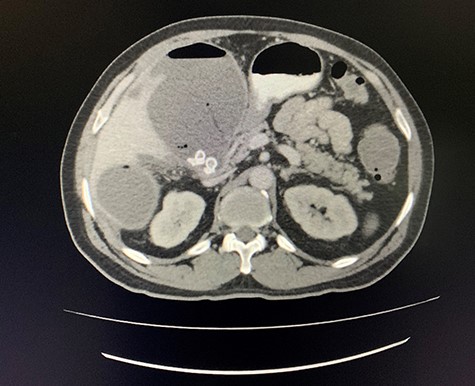

A computed tomography (CT) scan of the abdomen revealed an enlarged, thickened gallbladder with multiple stones, communicating with an intrahepatic collection in segment 4 measuring 116 × 80 mm, with an associated air fluid level and air locules (Fig. 1). There was an apparent fistulous tract to the hepatic flexure of the colon, another large collection in segment 6 (97 × 96 mm) as well as other smaller collections (Figs 2 and 3).

Coronal view of oral and intravenous contrasted CT scan of the abdomen demonstrating features of cholecystitis with fistulous communication with the hepatic flexure of the colon with associated pneumobilia.